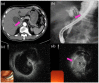

The diagnostic process for biliary strictures remains challenging in some cases. A broad differential diagnosis exists for indeterminate biliary strictures, including benign or malignant lesions. The diagnosis of indeterminate biliary strictures requires a combination of physical examination, laboratory testing, imaging modalities, and endoscopic procedures. Despite the progress of less invasive imaging modalities such as transabdominal ultrasonography, computed tomography, and magnetic resonance imaging, endoscopy plays an essential role in the accurate diagnosis, including the histological diagnosis. Imaging findings and brush cytology and/or forceps biopsy under fluoroscopic guidance with endoscopic retrograde cholangiopancreatography (ERCP) are widely used as the gold standard for the diagnosis of biliary strictures. However, ERCP cannot provide an intraluminal view of the biliary lesion, and its outcomes are not satisfactory. Recently, peroral cholangioscopy, confocal laser endomicroscopy, endoscopic ultrasound (EUS), and EUS-guided fine-needle aspiration have been reported as useful for indeterminate biliary strictures. Appropriate endoscopic modalities need to be selected according to the patient's condition, the lesion, and the expertise of the endoscopist. The aim of this review article is to discuss the diagnostic process for indeterminate biliary strictures using endoscopy.